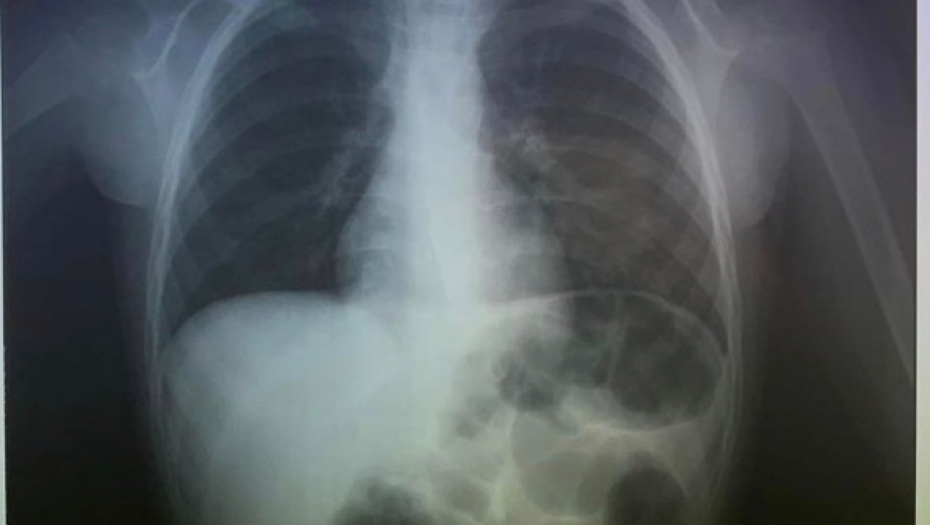

Doktori su prvo uradili rendgen, kako bi videli gde je završio novčić i videli da se zaglavio u grlu.

Doktori su na Fejsbuku objavili fotografije nakon intervencije.

"Oprostili smo se od 2023. godine hitnim vađenjem novčića koji je progutao dečak (4). Srećna Nova godina", napisali su oni.